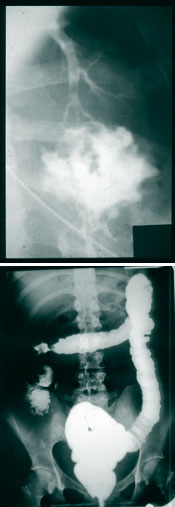

Chez les enfants, les conséquences de la maladie de Crohn peuvent être dévastatrices. La moitié des malades doivent subir une chirurgie qui peut aller jusqu’à l’ablation de segments de l’intestin. Ils ressentent des douleurs parfois très intenses à l’abdomen, souffrent de diarrhée chronique et de fièvre, et perdent du poids. Des complications peuvent survenir chez plusieurs enfants avant même que la maladie soit diagnostiquée.